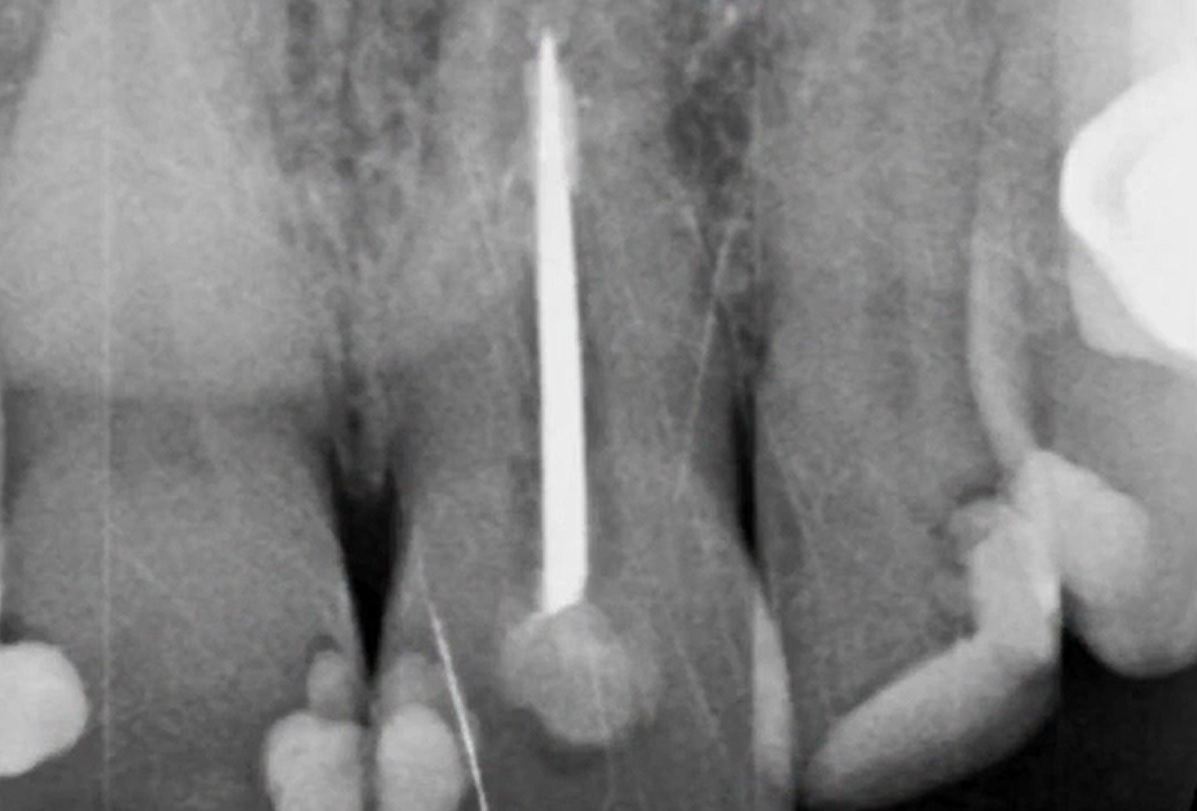

Dr Segin Chandran,Single replacement,Bone regeneration,Digital Guided Surgery,Maxillary Posterior,#25,Immediate Placement,Sinus Elevation,Guided surgery,AnyRidge,R2GATE Guide,R2GATE Surgical Kit(AnyRidge),MICA,Crestal elevation,Minimally invasive,Video